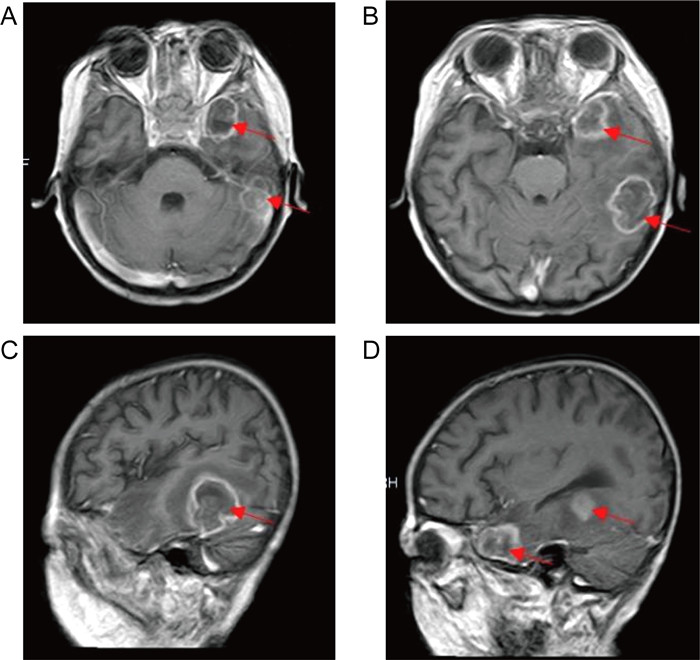

1.3 病情变化及预后患儿入院即存在中性粒细胞缺乏伴发热,感染控制后予以诱导缓解治疗(VDLD):长春新碱(vincristine)+柔红霉素(daunorubicin)+培门冬(pegaspargase)+地塞米松(dexamethasone)。患儿第13天再次出现发热,多次调整抗感染方案,先后曾给予美洛培南、万古霉素、伏立康唑、卡泊芬净、两性霉素B等抗感染治疗,体温控制欠佳,无热期1~2天,C反应蛋白(C-reactive protein,CRP)最高升至216 mg/L,降钙素原为2.27 ng/mL。期间多次完善胸部计算机断层扫描(computed tomography,CT)、腹部超声,均未提示明确异常。血培养、骨髓培养、脑脊液培养提示无菌生长,1,3-β-D葡聚糖抗原检测及半乳甘露聚糖抗原检测试验(G/GM试验)结果为阴性。VDLD诱导缓解治疗第19天患儿诉上门齿疼痛,经口腔科会诊及颌面部超声检查未提示明显异常,VDLD治疗第30天患儿出现左侧眼睑肿胀,伴有少量分泌物,给予妥布霉素滴眼液滴眼。VDLD诱导缓解治疗完成后第2天,患儿出现右侧鼻出血,左侧鼻腔流涕,且伴有喉中痰鸣,完善痰培养,并于耳鼻喉科行鼻腔镜检查,镜下双侧鼻腔可见血痂、干酪样物质,右侧中鼻甲、鼻中隔黏膜糜烂、吸收、缺如,骨质裸露、部分缺损,中鼻道霉菌团块,后鼻孔见坏死性干痂(见图 1),鼻腔分泌物行涂片检查: 找到真菌无隔菌丝(见图 2),分泌物及痰培养提示霉菌生长(见图 3)。急查头颅CT,见左侧颞叶低密度。行头颅磁共振成像(magnetic resonance imaging,MRI)平扫+增强,提示:左侧颞叶多发异常信号,右侧基底节区及左侧颞叶多发弥散受限灶,右侧颞叶病变内强化灶;蝶窦、左侧鼻腔、左侧上额窦、筛窦信号增高,结构欠清,前额部部分软脑膜明显强化,结合患者的病史,考虑真菌感染可能性大(见图 4)。患儿发热期间曾给予两性霉素B静滴,终因肾功能损害及低钾血症而暂停应用。患儿鼻眶脑型毛霉菌病诊断明确后立即给予两性霉素B脂质体(锋克松)静点,初始剂量0.5 mg/kg/d,逐渐增至2.5 mg/kg/d维持,同时予泊沙康唑90 mg/次,一日4次口服;期间给予两性霉素B雾化及鞘内注射,鞘内注射初始剂量为0.1 mg,逐渐增加至最大1 mg,每周2~3次,出院前共鞘注7次,两性霉素B总量为3.55 mg,期间因患儿头痛、血压高而减少鞘注剂量。患儿在接受两性霉素B脂质体抗真菌治疗期间出现肾功能损害及低血钾,予以调整两性霉素B脂质体剂量及静脉补钾治疗。应用两性霉素B脂质体抗真菌治疗后患儿热峰降低,C反应蛋白降至15 mg/L,左侧眼睑肿胀减轻,精神状态较之前明显好转,但患儿出现左侧上睑下垂,左眼球活动障碍,双侧瞳孔不等大,视物不清,复查头颅磁共振增强扫描,提示:脑内多发异常信号,右侧基底节区病变略缩小,余病变较前增大(见图 5), 建议家属待患儿血象恢复后手术切除感染灶,家属要求出院,院外继续口服泊沙康唑,未行手术及化疗,半年后死于白血病复发。

| 图 1 鼻腔镜检查 Fig. 1 Nasal endoscopy examination |

| Red arrow: Signal abnormality. 图 4 头颅磁共振增强扫描 Fig. 4 Brain enhanced magnetic resonance imaging |

| Red arrow: Signal abnormality. 图 5 头颅磁共振增强扫描复查 Fig. 5 Reexamination of brain enhanced magnetic resonance imaging |